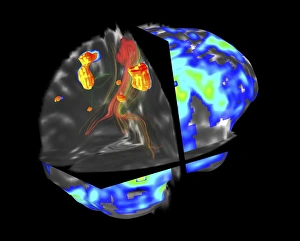

The central nervous system, the intricate network that governs our every thought and movement, is a marvel of complexity. From the delicate cerebellum tissue to the detailed light micrograph capturing its essence, we are reminded of its importance in maintaining balance and coordination. Anatomy comes alive as we explore the human brain from an inferior view. The intricacy of brain fibers is revealed through DTI MRI scans like C017/7099 and C017/7035, showcasing their vital role in transmitting information throughout this extraordinary organ. Artistic renderings bring us closer to understanding the medulla oblongata's significance within the brain. Its portrayal in various artworks allows us to appreciate how it controls essential functions such as breathing and heart rate. As we delve deeper into studying the central nervous system, models of the human brain provide invaluable insights into its structure and organization. Lateral views reveal countless regions responsible for cognition, emotion regulation, sensory perception, and motor control. Microscope slides offer glimpses into nerve cells' intricate architecture—a testament to their ability to transmit electrical signals at lightning speed. Meanwhile, glial stem cell cultures captured under a light microscope remind us of their crucial role in supporting neuronal function. Finally, artistic representations unveil the limbic system's enigmatic nature—an interconnected web responsible for emotions and memory formation. These captivating artworks allow us to visualize this complex network within our brains. Exploring these hints provides a glimpse into the awe-inspiring world of our central nervous system—the very foundation upon which our thoughts, actions, memories reside—reminding us just how remarkable our brains truly are.